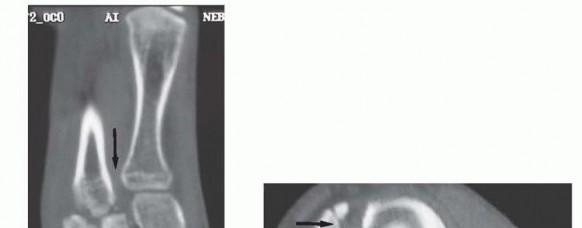

Computed tomography (CT) scanning may also be beneficial in the instance of a subtle Lisfranc injury, particularly in a polytrauma patient or a patient with multiple extremity injuries that preclude weight-bearing radiographs, and in delineating proximal fracture line extension into the navicular, cuboid, or cuneiforms (

FIG 4

).

• CT scan showing displacement through second tarsometatarsal and intercuneiform articulations (

A

) and intra-articular fractures of navicular and cuboid (

B

,

black arrows

) in a different patient.